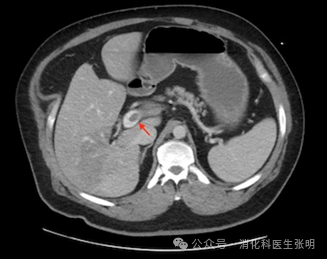

图片

肠系膜上静脉内的血栓